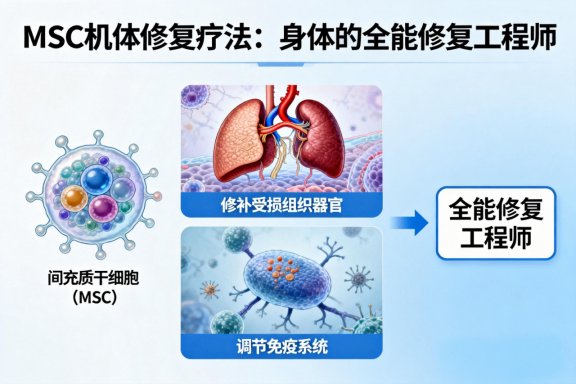

MSC机体修复疗法

MSC机体修复疗法

2

六大核心业务

国际领先六大肿瘤疗愈体系,确保每一位肿瘤患者得到超越预期的肿瘤疗愈,康复,终身健康保障服务。中美国际肿瘤连锁:郑州誉美肿瘤医院,武汉名逸肿瘤医院、博鳌华侨肿瘤医院。

细胞生物涉及两个细胞领域:细胞基因和胚胎干细胞产业化开发